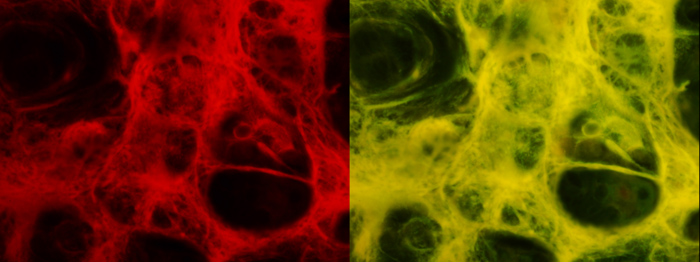

1)動脈の壁 (中膜)

Optiphoto 対物x40 撮像 x2.5 LED電流 0.2A

カメラ Lumix DMC-G5 左G励起 iso 400 露出時間 1sec, 右B励起 iso

800 露出時間 1sec